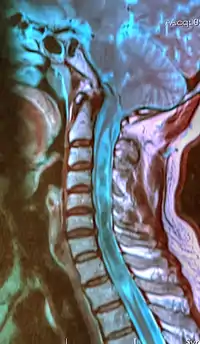

| A sagittal FLAIR MRI scan, from a patient with an Arnold–Chiari malformation, demonstrating tonsillar herniation of 7 mm. | |

Diagnosis is made through a combination of patient history, neurological examination, and medical imaging.[20][21] Magnetic resonance imaging (MRI) is considered the preferred imaging modality for Chiari malformation.[22] The MRI visualizes neural tissue such as the cerebellar tonsils and spinal cord as well as bone and other soft tissues. CT and CT myelography are other options and were used prior to the advent of MRI, unfortunately the resolution of CT based modalities do not characterize syringomyelia and other neural abnormalities as well.[23]

By convention, the cerebellar tonsil position is measured relative to the basion-opisthion line, using sagittal T1 MRI images or sagittal CT images.[24] The selected cutoff distance for abnormal tonsil position is somewhat arbitrary, as not every person will be symptomatic at a certain amount of tonsil displacement, and the probability of symptoms and syrinx increases with greater displacement; however, greater than 5 mm is the most frequently cited cutoff number, though some consider 3–5 mm to be "borderline"; pathological signs and syrinx may occur beyond that distance.[24][25][26] One study showed little difference in cerebellar tonsil position between standard recumbent MRI and upright MRI for patients without a history of whiplash injury.[18] Neuroradiological investigation is used to first rule out any intracranial condition that could be responsible for tonsillar herniation. Neuroradiological diagnostics evaluate the severity of crowding of the neural structures within the posterior cranial fossa and their pressure against the foramen magnum. Chiari 1.5 is a term used when both brainstem and tonsillar herniation through the foramen magnum are present.[27]